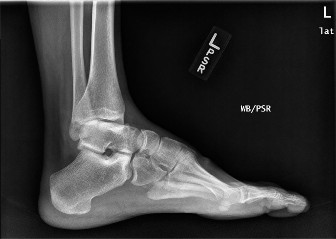

A 22-year-old female presents complaining of pain along the lateral border of her left foot. She has a known …